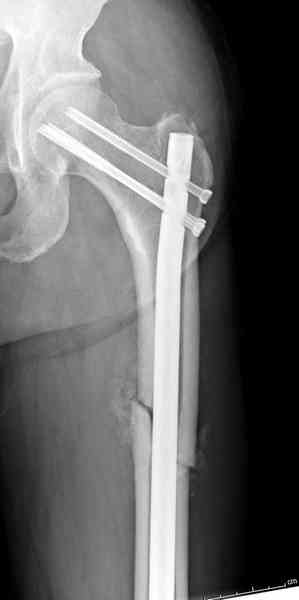

Здесь представлены снимки больного 65 лет, поступившего с диагнозом перелом

бедра после автоаварии.

В первый же день произведено антеградное штифтованием DePuy Trochanteric Nail.

На второй день (7) обнаружен пропущенный перелом,

и проведены шурурпы через и спереди штифта без удаления.

Послеоперационные снимки